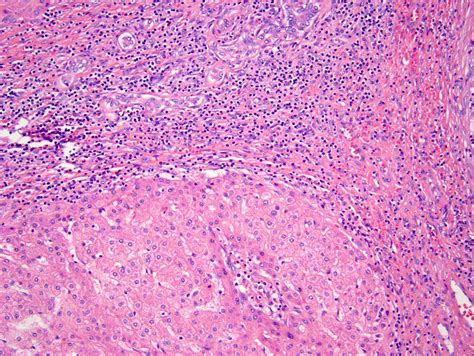

• Liver Biopsy: In some cases, a liver biopsy may be performed to confirm the diagnosis. This involves taking a small sample of liver tissue for examination under a microscope.